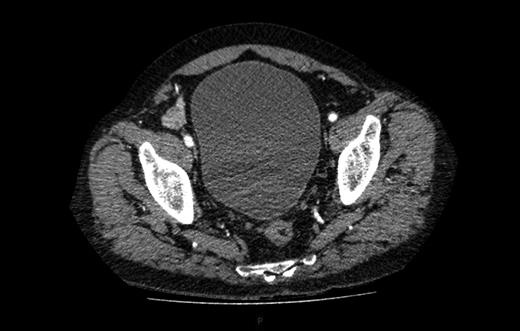

A computed tomography (CT) of the abdomen and pelvis was performed. This showed a grossly distended urinary bladder and compression of the sigmoid colon against the sacral promontory causing bowel obstruction (Figs 1 and 2, respectively) as well as a 4.9 cm abdominal aortic aneurysm without any signs of a rupture (Fig. 3). The plan was to consult our vascular colleagues regarding management of the AAA once the obstruction had settled.

Further image of the same CT scan showing compression of the sigmoid colon against the sacral promontory (see arrow) behind the distended bladder.

Abdominal aortic aneurysm with some wall standing thrombus but without any signs of rupture.